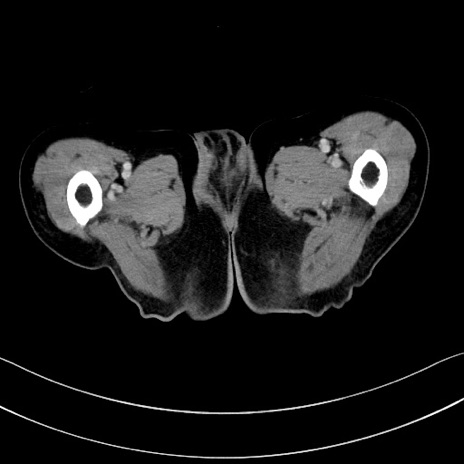

症例28(横断像)

【症例】60歳代男性

【現病歴】胃癌にて胃全摘後。食思不振が悪化し、夜中に嘔吐することがある。

【既往歴】胃癌、胃全摘、脾摘、胆摘後